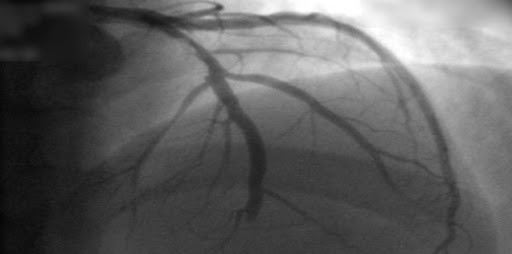

El tratamiento guiado por angiografíca coronaria por tomografía computada (ACTC) de los pacientes con dolor torácico estable se asoció con una reducción sostenida de la muerte por enfermedad coronaria o infarto de miocardio no mortal. La identificación de la aterosclerosis coronaria mediante ACTC mejora la prevención de la enfermedad cardiovascular a largo plazo en pacientes con dolor torácico estable. The Lancet, 25 de enero de 2025.

Estudios coronarios en la cardiopatía isquémica estable: ¿TC o cateterismo?

Este estudio no encontró diferencia entre mujeres y varones en el beneficio del uso de la tomografía computarizada (TC) en lugar de la angiografía coronaria invasiva como prueba diagnóstica inicial para el manejo del dolor torácico estable en pacientes con una probabilidad previa a la prueba intermedia de enfermedad arterial coronaria. La TC inicial se asoció con menos complicaciones importantes relacionadas con el procedimiento en las mujeres y una frecuencia más baja del compuesto MACE expandido en los hombres.British Medical Journal, 19 de octubre de 2022.